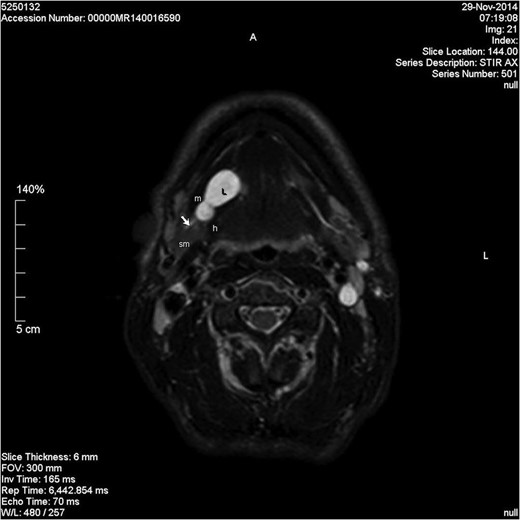

Axial STIR image showing a lobulated homogenous hyperintense lesion in the right floor of mouth. L, lesion; m, mylohyoid muscle; sm, submandibular gland; h, hyoglossus; short arrow, Wharton's duct.

Schwannoma is difficult to diagnose clinically but, a long-standing history and a firm mass are suggestive [4]. Radiological diagnosis can also be challenging with sensitivity estimated at 20% for computed tomography (CT) and up to 80% for MRI [5]. Ultrasonography is often used in the investigation of neck lumps. However, the appearance of a schwannoma can mimic a pleomorphic adenoma. The literature does not support the use of CT for the diagnosis of schwannoma and MRI is often preferred for better soft tissue delineation. This may aid in diagnosis and identification of the nerve of origin. Schwannomas appear hypointense on T1-weighted images and heterogeneously hyperintense on T2-weighted images [4, 6]. They demonstrate intense enhancement with gadolinium-based contrast. As demonstrated in our case, MRI can still fail to be diagnostic.

The differential diagnosis of a right-sided neck swelling is varied and includes: submandibular gland neoplasm, lymphadenopathy, plunging ranula, haemangioma and lipoma. A ranula is a retention cyst of the sublingual gland which usually occurs secondary to trauma or duct obstruction. It often presents as a bluish swelling in the floor of the mouth. The swelling can extend behind or through the mylohyoid muscle and into the submandibular space forming a plunging ranula [5]. A plunging ranula is usually associated with an intra-oral component but rarely it can present as an isolated neck swelling [5]. The pre-operative imaging of our patient demonstrated a homogenous, non-enhancing lesion involving the sublingual gland and extending into the submandibular space. The lesion did not show enhancement with contrast which is unusual for a schwannoma [8], and may be interpreted as being consistent with a cystic lesion. Both schwannomas and ranulas appear hypointense on T1-weighted images and hyperintense on T2-weighted images. As FNAC was inconclusive, a differential diagnosis of several pathologies was considered based on clinical assessment and radiological investigations. Given the characteristic MRI appearances and the failure to enhance with contrast, a pre-operative diagnosis of plunging ranula was made.